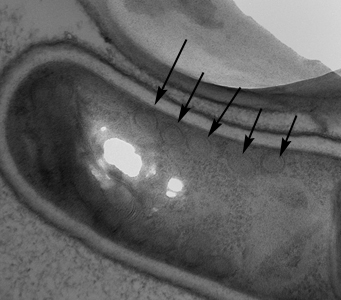

A 27-year-old HIV-positive male presented with abdominal pain and chronic diarrhea. He had a history of AIDS cholangiopathy. Recent microbiology results included bacteremia caused by Enterobacter species and sputum cultures positive for Mycobacterium avium-complex (MAC). During routine examination of Gram-stained bronchial alveolar lavage (BAL) specimens, suspect objects were observed by the attending technologist. Additional BAL material was stained with calcofluor white and Gram chromotrope, and the suspect objects were observed being positive for both. Images were captured of the BAL stained with Gram chromotrope (Figures A and B) and sent to the DPDx Team for diagnostic assistance. Additionally, the BAL specimen was forwarded on to the DPDx Team for additional work-up. The DPDx Team prepared a fresh smear from the BAL, stained with chromotrope 2R, and observed similar objects at 1000x with oil (Figures C and D), which measured approximately 2.0 micrometers in length. What is your diagnosis? Based on what criteria? What additional tests, if any, would you recommend?

Figure A